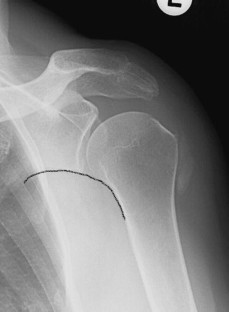

Abb. 2